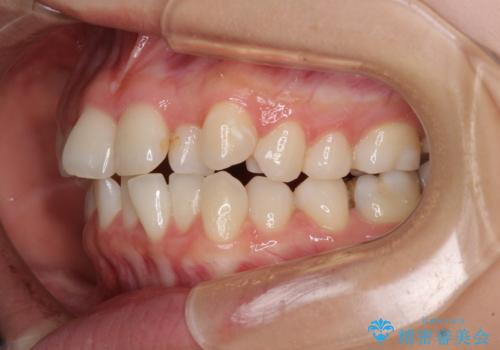

- 前歯のデコボコを気にして来院された患者様です。

前歯のデコボコはもちろん気になるところですが、舌の突出癖により上下の前歯に大きな隙間がある状態でした。

上下前歯が非接触である開咬は、インビザラインによる治療がお勧めではありますが、非抜歯矯正か抜歯矯正か悩む口元であり、途中抜歯矯正に切り替えたときに対応しやすいよう、ワイヤー装置にて治療を行うこととしました。